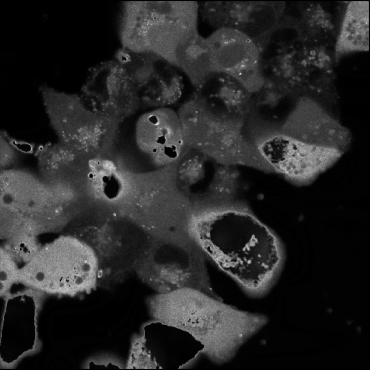

6.2 GT comparison

Samples of images generated using our pipeline were shown to an expert experimentalist for the selection of preprocessing-projection method combinations which could provide comprehensive, useful and different information about the cardiac cell networks imaged for GT annotation. Selected methods are shown in Figure 6. GT annotations generated using the selected projections were compared with annotations generated from composite grayscale images obtained using conventional frames stacking and averaging methods [7]. Due to visualisation constraints in old composite images due to low brightness and impaired image quality, only 77 images were analysed at this stage. New GT () and old GT () annotations were compared using two levels of analysis:

Pixel-Level Agreement (Semantic segmentation)

At this level, we evaluated the semantic agreement between and using several metrics: Intersection over Union (IoU), which measures the extent of overlap between the two GTs, Background Mismatch (BG ), which quantifies the percentage of pixels labelled as background in one GT but pertaining to foreground in the other. Results of these evaluations are presented in Table 3.

As illustrated in Table 3, we observed notable variance in IoU scores across the dataset. To better understand this variability, we visually examined three representative cases from and , one with the lowest IoU (Figure 6(a) and (d)), one with the highest (Figure 6(c) and (f)), and one approximating the metric’s median (Figure 6(b) and (e)). Our analysis revealed that images taken at higher microscope magnifications (Figure 6(c) and (f)) yielded higher IoU scores between and , indicating alignment between the two GTs. This suggests that increased resolution may facilitate consistent segmentation.

Metric IoU BG Mo BG Mn CA CA CC CC mean 86.08 6.86 5.15 4106 5452 47 74 p25 84.19 5.06 3.46 2354 3495 35 50 median 86.43 6.56 4.72 2820 4238 52 75 p75 88.69 8.31 6.06 4172 6174 61 91 min 75.89 1.52 1.64 1372 2503 12 11 max 92.40 15.13 14.36 21952 19286 84 171

Furthermore, in these high-magnification cases, provided clearer delineation of cellular boundaries and background regions, particularly at the image corners, where segmentation is typically more challenging. In the lowest IoU examples (Figure 6(a) & (d)), revealed more complete cell structures and extended boundaries, indicating improved visibility and segmentation accuracy.

Additionally, BG , which highlights instances where regions previously labelled as cells in were reclassified as background in , was found to be higher than BG , suggesting that noise reduction or enhanced visibility improved the accurate delineation of true cell regions in .

Cell-Level analysis (Instance segmentation)

This level focuses on instance-level comparisons. We examined metrics such as Cell Counts (CC), Cell Size (CS), and shape descriptors to assess structural differences between the GTs. The outcomes of this analysis are summarised in Table 3 and visualized in Figure 8, using Kernel Density Estimation (KDE) and box-plots.

The distribution of cell areas in exhibits a pronounced peak at smaller sizes, indicating that the new segmentation and preprocessing pipeline tends to produce a greater number of small cells, with many cell areas clustered around lower values. In contrast, the distribution for is broader, suggesting a wider range of cell sizes and less concentration around any particular value. This pattern implies that yields more consistent and generally smaller cell segmentations, whereas contains larger cells.

One of the key requirements for efficient image fusion is that the fused image must preserve all the quantitative information contained within the original video recording and contain more detailed information about the scene or object depicted than the isolated frames alone. Cell-level comparison of CA and CC in GTo and GTn annotations proved that images generated through the image fusion method presented in this study contain a higher number of cells, averaging a increase in cell count (from a median of 52 cells identified in to a median of 75 cells in ), than images generated using conventional frames stacking and averaging methods (Table 3 and Figure 2b). These results suggest two main things: 1) our pipeline is more effective than previously employed methods [7] at combining data from multiple frames while reducing temporal inconsistencies across frames caused by fluctuating fluorescence signal intensity within cells. Therefore, projected images generally retain more complete information about the cellular network for downstream annotation (Figure 8); 2) efficient noise removal and contrast enhancement by our proposed approach improves the visibility of cellular boundaries, facilitating the separation of individual cells within dense and overlapping cellular regions characterised by cellular aggregation (Figure 7). This last assumption is further corroborated by the results achieved from the analysis of pixel-level agreement between GTo and GTn. By comparing BG and BG (Table 3), is therefore evident that a higher percentage of pixels identified as cells in GTo were changed to background pixels in GTn than vice-versa. This shift suggests that noise was either removed by our projection pipeline or that improved visibility and image sharpness, especially around cellular boundaries, enabled more accurate identification of true cell regions. Therefore, as shown in Figure 7a and 7d, large cells in were often segmented into multiple smaller cells in , likely due to enhanced boundary detection. This is also suggested by the lower CA and higher cellular density recorded in than (Figure 8), where the lower amount of larger cells recorded in suggests the under-segmentation of low-brightness cellular regions with unclear boundaries from unprocessed composite grayscale images. Overall, these observations support the hypothesis that the revised preprocessing pipeline produces more precise and biologically consistent segmentations.